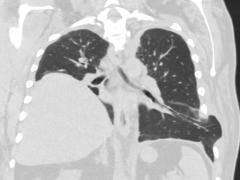

Een man die de longen uit z’n lijf hoest